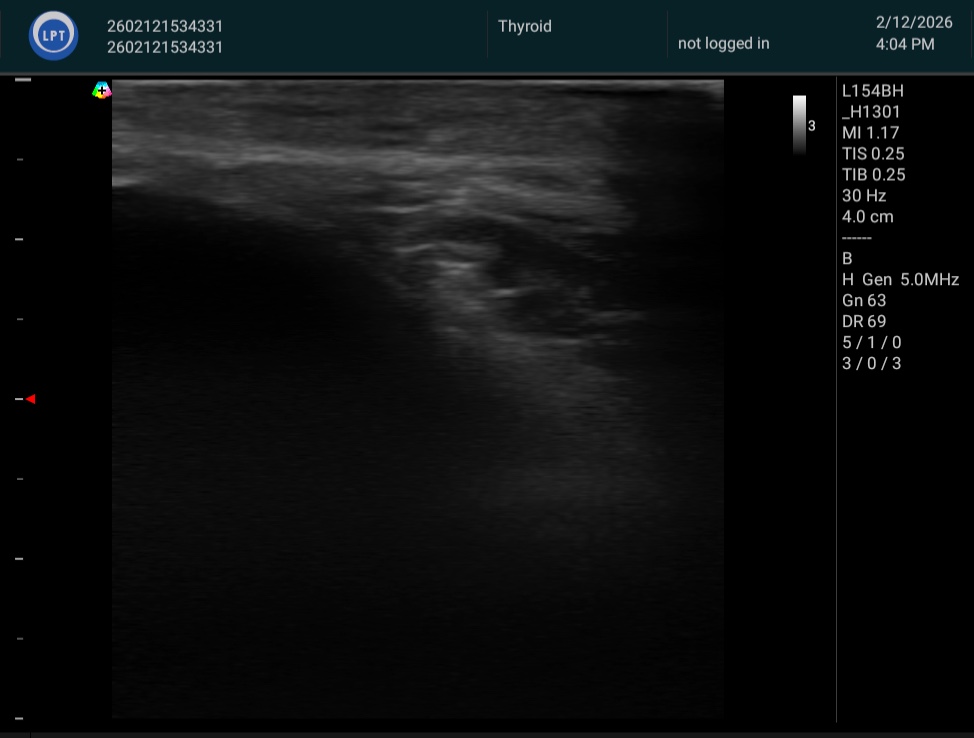

施術前後の変化をエコー画像・ノギス計測によって客観的に記録しています。

脂肪体が「膨らむ」——その事実を、数字と画像がそのまま示しています。

すべて、たった1回の施術後の計測です。

※ 個人差があります。掲載の計測値はすべて実際の施術前後の計測結果です。

※ エコー画像・ノギス計測は施術効果の参考として提示しています。